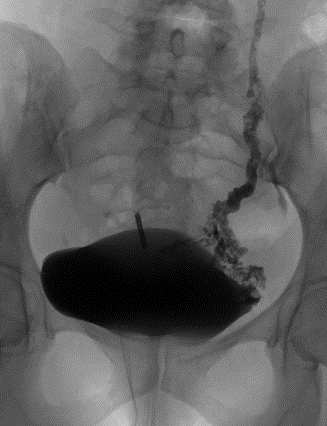

- Contrôle final montrant l’embolisation des varices et de la veine ovarienne gauche responsable du reflux.

Par ponction d’une veine du bras ou de l’aine, le radiologue va réaliser un bilan vasculaire des varices grâce à un cathéter et une injection de produit de contraste sous contrôle radiographique. - Un deuxième temps thérapeutique : l’Embolisation

Les varices sont bouchées et la cause du reflux est traitée par injection d’un agent d’embolisation (coils, sclérosant, onyx, colle), ou mise en place d’un stent.